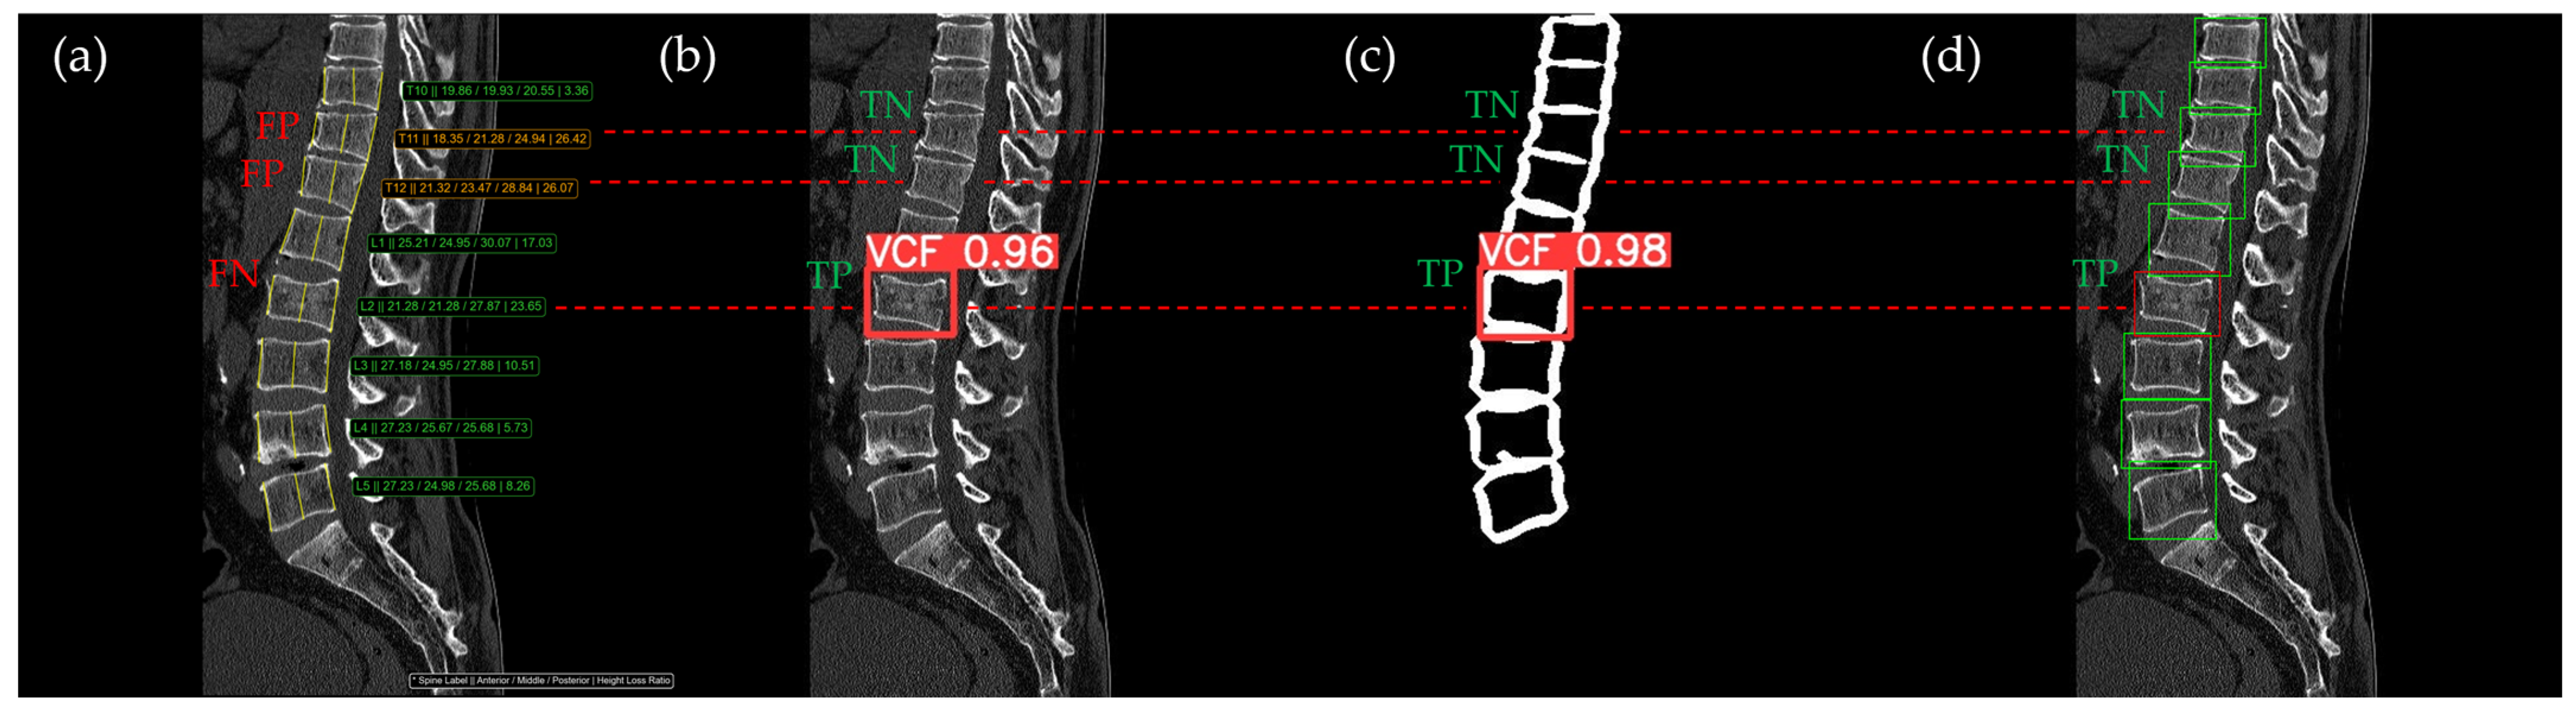

Figure 10, Figure 11, Figure 12, Figure 13 and Figure 14 illustrate typical examples of results for HLR, EEVD, TSVD_SD, and TSVD_DC in patients with acute VCFs. The results of applying different methodologies to the same patient image and identical slice locations were as follows. In the HLR results, each vertebra was marked with yellow solid lines indicating the height measurement lines for the anterior, middle, and posterior regions. The measured height values and HLR percentages were displayed on the right side of the image. If the HLR percentage ranged between 25% and 40%, it was highlighted in orange, while values of 40% or higher were highlighted in red. In the EEVD results, the VCF detection outputs were displayed along with their respective confidence scores based on the input patient images. For the TSVD_SD results, after performing spine segmentation, the model extracted only the spine contour, and the VCF detection results with their corresponding confidence scores were presented. In the TSVD_DC results, bounding boxes were generated for each vertebral body, with normal vertebrae represented in green and vertebrae identified as VCFs displayed in red.

In Figure 12, the L1 vertebra was identified as having an acute VCF, while L4 was determined to be normal. At L1, there was cortical breakage and step-off at the anterior lower region. The HLR method failed to detect this VCF, while EEVD, TSVD_SD, and TSVD_DC successfully identified it. In the HLR assessment, L4 exhibited physiological wedging, with the posterior height measuring more than 25% lower than the anterior and middle heights. Due to the S-shaped curvature of the human spine, it is common for the posterior height to be slightly lower in the L4–L5 region. Consequently, EEVD, TSVD_SD, and TSVD_DC did not classify L4 as a VCF (TN).

Figure 12. The VCF detection results from four different methods. (a) HLR, (b) EEVD, (c) TSVD_SD, and (d) TSVD_DC. The acute VCF, as confirmed by the radiologist, was located at the L1 level. TP, TN, FP, and FN were marked at the same level with a red dotted line.